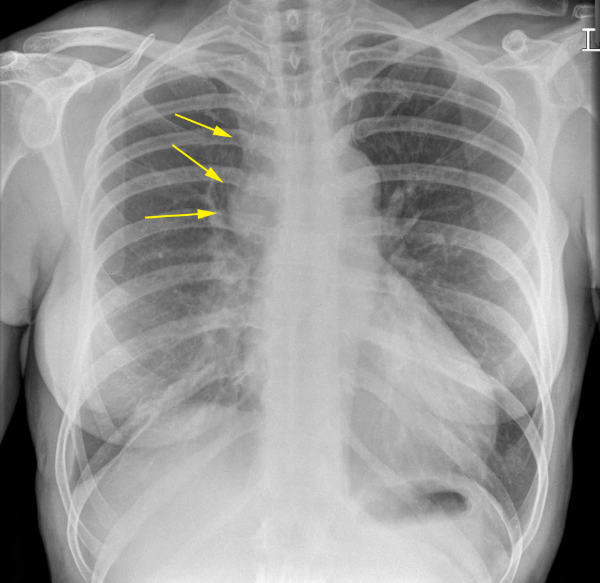

This patient has hyponatraemia. What is shown?

Right paratracheal mass. This is likely to be malignant – it may represent adenopathy or a paratracheal mass lesion (look at the image below – arrows show mass).